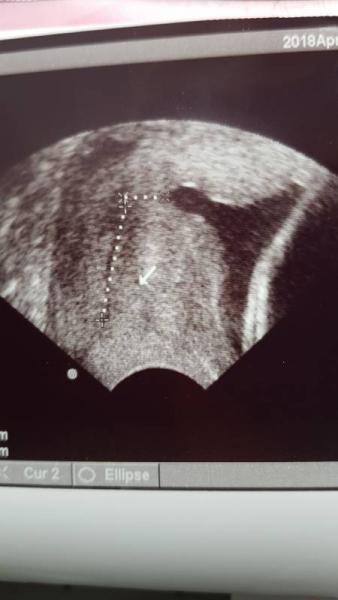

Guck mal bei mir war das 26+ also ziemlich Theater im Bauch, es ist mein 6 Kind und ich kenne es von allen anderen auch vorher. Selbst mit einer restzervix von 5 mm und riesiger Trichter blieb meine Liane bis 37+6 im Bauch. Ich bekam bei 4 von 5 Tokolyse und lungenreife. Das US-Bild ist von jetzt. Es war nicht mehr viel GMH (2,3 cm) aber bei uns hat sich alles erholt. Magnesium ja regelmässig (obwohl schon einige studien belegen, echte geburtswehen lassen sich auch damit nicht aufhalten) und es macht bei zu viel Durchfall, welcher durch die Darmtätigkeit auch zu Wehen führen kann. Bryophyllum kann ich auch nur empfehlen. Lungenreife habe ich z.b bei der letzten nicht geben lassen und die blieb bis 39+6 am längsten drin.